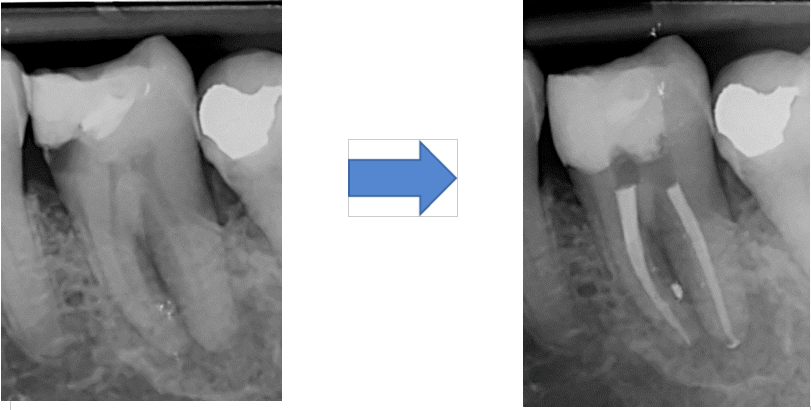

On voit ici à gauche la radiographie de la dent avant le traitement endodontique, puis à droite la radiographie de la même dent après le traitement. Les racines ont été remplies par un matériau visible en blanc, qui va bloquer la prolifération et la propagation des bactéries dans le corps.